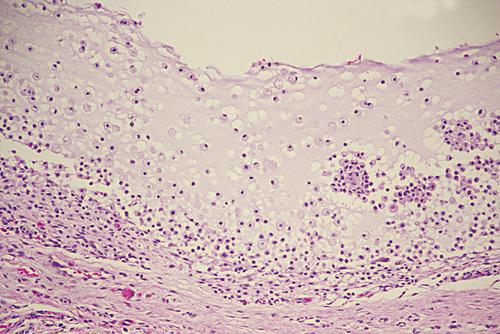

High-power view showing spilled mucin that is associated with granulation tissue containing foamy histiocytes.

mucocele